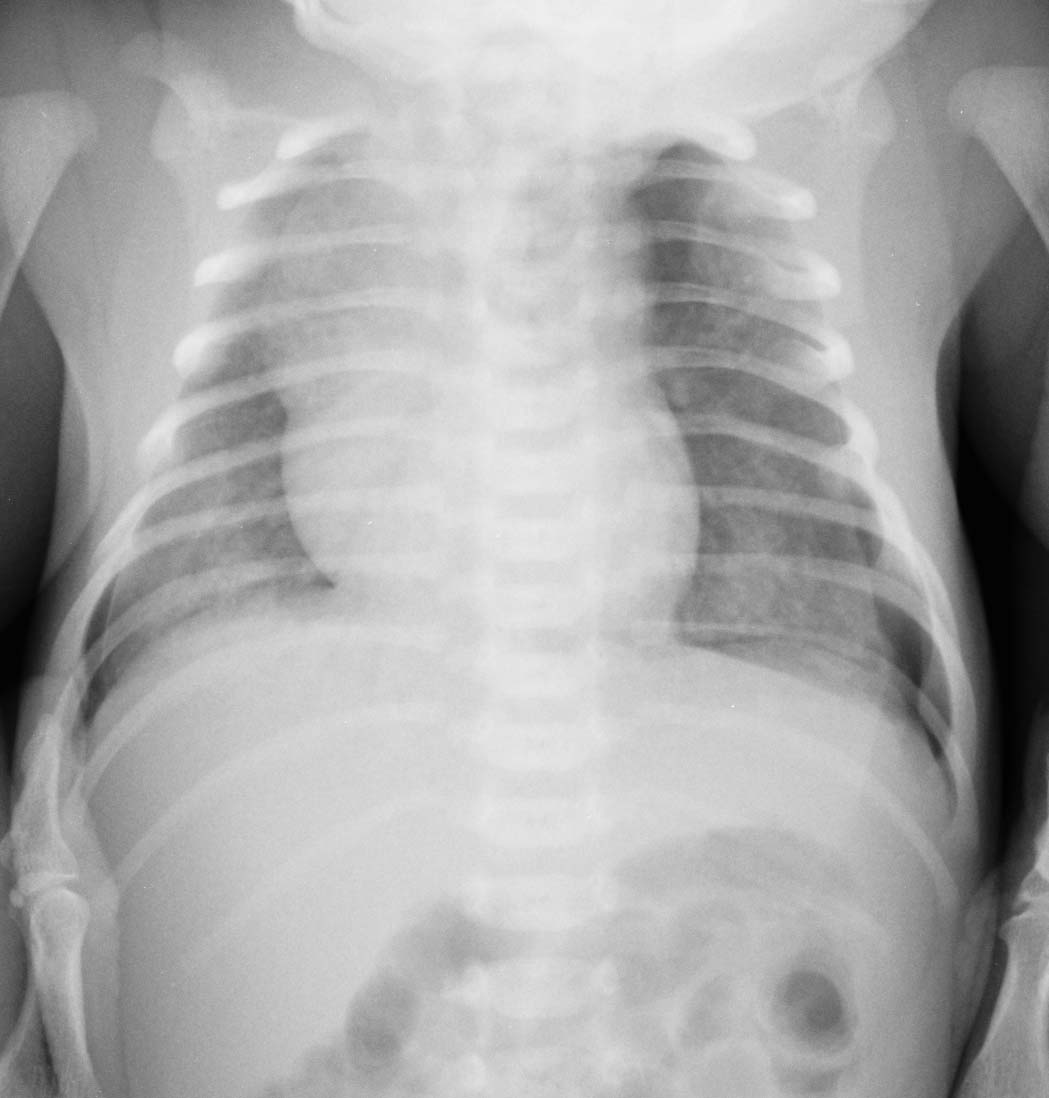

未处理第2天

肺透明膜病伴气胸

不是气胸,由于是仰卧位摄片,背部的皮肤皱褶造成的假象,这种情况在成人也可出现,若不注意,很容易误为气胸.若平时注意观察,这种例子时有见到.